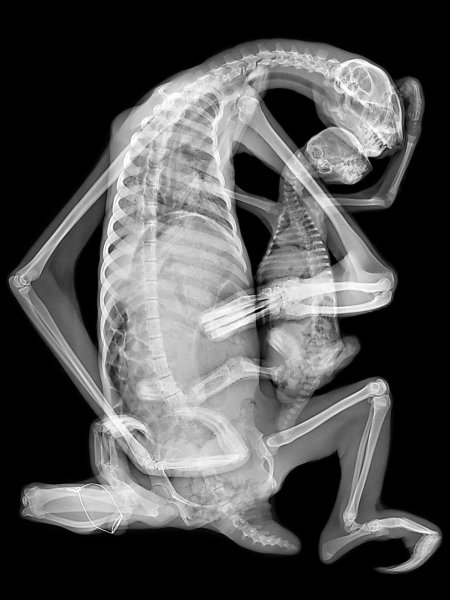

Рентгеновский эффект создает фантастические композиции в этих фотографиях девушки, чье тело становится прозрачным, демонстрируя скелет и внутренние органы. Она позирует в разных позах, ее силуэт светится загадочным свечением. Каждый кадр передает атмосферу научной фантастики и медицинского искусства. Ее кожа кажется полупрозрачной, позволяя увидеть кости и мышцы. Фотографии рассказывают о хрупкости человеческого тела и его внутренней красоте. Девушка то стоит в задумчивости, то делает грациозное движение. Эти иллюстрации вдохновляют на размышления о человеческой анатомии и уязвимости. Каждая картинка - это момент прозрения, когда внешнее уступает место внутреннему. Девушка воплощает образ современной Медузы, сочетающей красоту и загадочность.

Сквозь материю: тайны анатомии